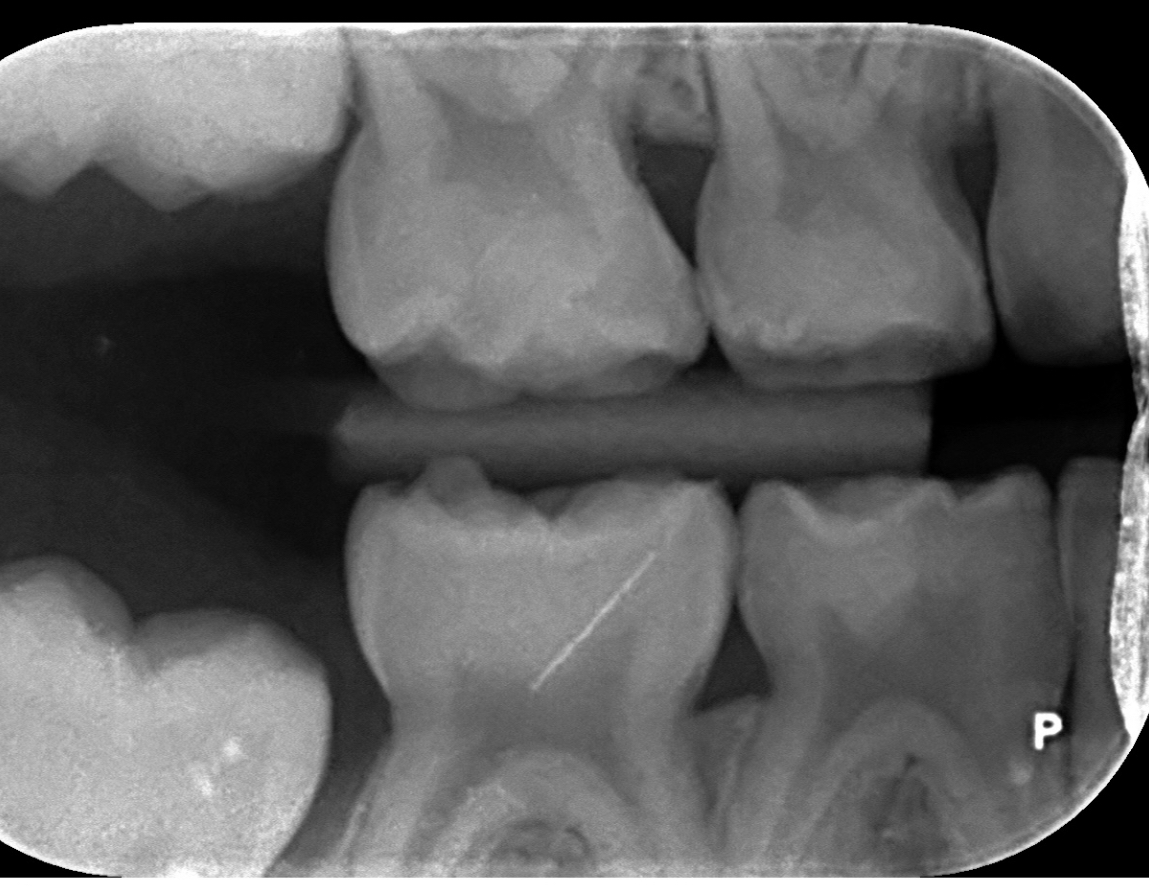

Beste tandartsen, Deze week hebben wij te horen gekregen dat mijn zoontje 3 gaatjes in zijn melkkiesjes heeft. Onze tandarts heeft een voorkeur voor RVS kronen op alle drie de getroffen kiesjes, maar het is ons niet helemaal duidelijk in hoeverre dit is vanwege het effect van de ingreep op een 6 jarige an sich, of de mate waarin de gaatjes gevorderd zijn. Ik zou graag begrijpen welke kiesjes zijn aangedaan en bij welke vullen eventueel mogelijk is (ik zou RVS kronen heel graag willen voorkomen… voornamelijk op de voorste kiesjes die erg goed zichtbaar zijn bij hem). Kunnen jullie dit helpen beoordelen per aangedaan kiesje ahv bijgesloten foto’s? Bedankt!

Ik kan een x-foto normaal in mijn programma bewerken. Deze foto's niet . Maar mogelijk 6 gaatjes die ik gewoon vull, uitgaande v wat ik op de foto zie. Maar pas duidelijk als ik ook in de mond beoordeel.64/65/74/54/55/84.